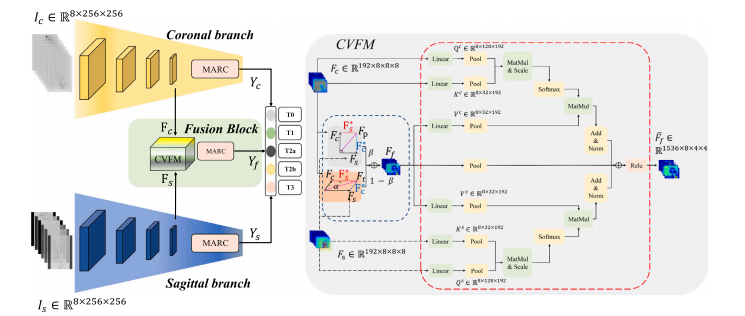

The modified Thrombolysis In Cerebral Infarction (mTICI) score serves as one of the key clinical indicators toassess the success of the Mechanical Thrombectomy (MT), requiring physicians to inspect Digital SubtractionAngiography (DSA) images in both the coronal and sagittal views. However, assessing mTICI scores manuallyis time-consuming and has considerable observer variability. An automatic, objective, and end-to-end methodfor assigning mTICI scores may effectively avoid observer errors. Therefore, in this paper, we propose a novelCross View Fusion Scoring Network (CVFSNet) for automatic, objective, and end-to-end mTICI scoring, whichemploys dual branches to simultaneously extract spatial–temporal features from coronal and sagittal views.Then, a novel Cross View Fusion Module (CVFM) is introduced to fuse the features from two views, whichexplores the positional characteristics of coronal and sagittal views to generate a pseudo-oblique sagittal featureand ultimately constructs more representative features to enhance the scoring performance. In addition, weprovide AmTICIS, a newly collected and the first publicly available DSA image dataset with expert annotationsfor automatic mTICI scoring, which can effectively promote researchers to conduct studies of ischemic strokebased on DSA images and finally help patients get better medical treatment. Extensive experimentation resultsdemonstrate the promising performance of our methods and the validity of the cross-view fusion module.

改良的脑梗死溶栓分级(mTICI)评分是评估机械取栓术(MT)是否成功的关键临床指标之一,这要求医生同时检查冠状位和矢状位的数字减影血管造影(DSA)图像。然而,手动评估mTICI评分既耗时,又存在相当大的观察者之间的差异。一种自动、客观且端到端的mTICI评分方法可能会有效地避免观察者带来的误差。 因此,在本文中,我们提出了一种新颖的跨视图融合评分网络(CVFSNet),用于自动、客观且端到端地进行mTICI评分。该网络采用双分支结构,同时从冠状位和矢状位图像中提取时空特征。然后,引入了一种新颖的跨视图融合模块(CVFM)来融合来自两个视图的特征,该模块探究了冠状位和矢状位视图的位置特征,以生成伪斜矢状位特征,并最终构建出更具代表性的特征,从而提升评分性能。 此外,我们提供了AmTICIS数据集,这是一个新收集的、首个带有专家标注的公开可用的DSA图像数据集,用于自动进行mTICI评分。该数据集能够有效地推动研究人员基于DSA图像开展缺血性中风的相关研究,并最终帮助患者获得更好的治疗。大量的实验结果证明了我们所提出方法的出色性能以及跨视图融合模块的有效性。

We proposed a CVFSNet based on dual-view angiographic imagesfor automatic, objective, end-to-end mTICI scoring and built a crossview fusion module, CVFM, to integrate, aggregate, and complementfeatures from different views. In the ablation experiments, we firstcompared the performance between single-view and dual-view inputs,demonstrating the necessity of dual-view image input. This may bedue to the fact that DSA imaging is projection-compressed and intracranial vessel structures are complex, leading to vessel overlap insingle-view images, which affects the model’s ability to characterizeblood flow accurately. Then, by comparing different methods of dualview feature fusion, we verified the effectiveness of the CVFM module.CVFM leverages prior positional knowledge of coronal and sagittalviews, constructs oblique sagittal features using trigonometric functionsand the Pythagorean theorem, and employs a transformer-like moduleto explore complementary relationships between coronal and sagittalfeatures, thereby building global dependencies and generating more expressive fused features, ultimately enhancing performance. In the comparative experiments, we compared our approach with some classicaland state-of-the-art video feature classification models, demonstratingsuperior performance andgood stability.In the dichotomized experiments, CVFSNet demonstrated performance exceeding 90% across all indicators, implying that CVFSNet mayhave the potential for clinical application in determining the adequacyof mTICI scores. However, our study also has limitations. Firstly, thesevideo feature classification methods that were compared in the comparative experiments only supported single-view inputs, which maydisadvantage their comparison in terms of performance. Additionally,the AmTICIS dataset constructed in this study only includes data forM1 segment stenosis, limiting its clinical applicability. In the future,we plan to expand the dataset to include more mTICI scoring datawith various vessel stenosis, such as Internal Carotid Artery (ICA), BaseArtery (BA), Anterior Cerebral Artery (ACA), and Posterior CerebralArtery (PCA) etc., thereby constructing a more comprehensive scoringdataset. Also, the sample size of AmTICIS can be further expanded byincorporating data from multiple centers to enhance its diversity.In conclusion, we propose a novel CVFSNet in this paper for automatic, objective, and end-to-end mTICI scoring. Specifically, CVFSNetemploys dual branches to simultaneously extract spatial–temporal features from coronal view and sagittal view, and these cross-view featuresare fused through a novel cross view fusion module that explores thepositional characteristics of coronal and sagittal views to fuse andgenerate a pseudo-oblique sagittal feature and deploys a transformerlike architecture to explore the correlation between different viewfeatures, ultimately constructing more representative features to enhance the scoring performance of the model. In addition, we providea newly collected and the first publicly available digital subtractionangiography image dataset with expert annotations (AmTICIS) for automatic mTICI scoring, which can effectively promote researchers toconduct studies of ischemic stroke based on DSA images and finallyhelp patients get better medical treatment. Extensive experimentationresults demonstrate the promising performance of our methods and theeffectiveness of the cross-view fusion module.

我们基于双视角血管造影图像提出了CVFSNet网络,用于实现自动、客观、端到端的脑梗死溶栓治疗改良分级(mTICI)评分,并构建了一个跨视角融合模块(CVFM),以整合、聚合和补充来自不同视角的特征。在消融实验中,我们首先比较了单视角输入和双视角输入的性能,结果表明了双视角图像输入的必要性。这可能是因为数字减影血管造影(DSA)成像是投影压缩的,且颅内血管结构复杂,导致单视角图像中出现血管重叠,从而影响了模型准确表征血流的能力。然后,通过比较不同的双视角特征融合方法,我们验证了CVFM模块的有效性。CVFM利用冠状面和矢状面的先验位置知识,使用三角函数和勾股定理构建斜矢状面特征,并采用类似Transformer的模块来探索冠状面和矢状面特征之间的互补关系,从而建立全局依赖关系,并生成更具表现力的融合特征,最终提升性能。在对比实验中,我们将我们的方法与一些经典的以及最先进的视频特征分类模型进行了比较,结果显示出我们的方法具有优越的性能和良好的稳定性。 在二分类实验中,CVFSNet在所有指标上的表现均超过了90%,这意味着CVFSNet在确定mTICI评分是否足够方面可能具有临床应用潜力。然而,我们的研究也存在局限性。首先,在对比实验中所比较的这些视频特征分类方法仅支持单视角输入,这在性能比较方面可能对它们不利。此外,本研究构建的AmTICIS数据集仅包含大脑中动脉M1段狭窄的数据,限制了其临床适用性。未来,我们计划扩展该数据集,纳入更多具有各种血管狭窄情况的mTICI评分数据,例如颈内动脉(ICA)、基底动脉(BA)、大脑前动脉(ACA)和大脑后动脉(PCA)等,从而构建一个更全面的评分数据集。同时,通过纳入多个中心的数据来进一步扩大AmTICIS的样本量,以提高其多样性。 总之,本文提出了一种新颖的CVFSNet网络,用于自动、客观、端到端的mTICI评分。具体而言,CVFSNet采用双分支同时从冠状面和矢状面提取时空特征,并且这些跨视角特征通过一个新颖的跨视角融合模块进行融合。该模块探索冠状面和矢状面的位置特征,以融合并生成伪斜矢状面特征,并部署了类似Transformer的架构来探索不同视角特征之间的相关性,最终构建出更具代表性的特征,以提升模型的评分性能。此外,我们提供了一个新收集的、首个带有专家注释的公开可用的数字减影血管造影图像数据集(AmTICIS),用于自动mTICI评分,这可以有效地推动研究人员基于DSA图像开展缺血性中风的研究,并最终帮助患者获得更好的治疗。大量的实验结果证明了我们方法的良好性能以及跨视角融合模块的有效性。

Fig. 4. Overall schematic diagram of CVFSNet and CVFM.

图4:跨视图融合评分网络(CVFSNet)以及跨视图融合模块(CVFM)的整体示意图。